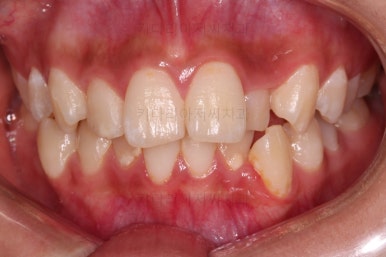

동래교정치과 초진 시의 입 안 모습이에요.

치열이 삐뚤고 덧니가 보이네요.

이번 환자분도 스스로는 보기 싫은 이유가 첫 번째였지만 사진에서도 보시다시피 양치가 잘 안되어 치석도 많고 잇몸도 부어있는 상태였어요.

그리고 앞니들이 마모가 많이 되어 있어서 각각의 치아들이 원래 형태에서 많이 변형된 것을 볼 수 있네요.